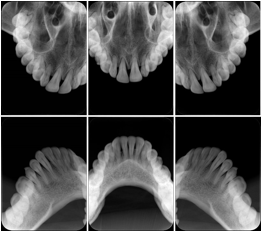

2 Occlusal Vertical Maxilla A Dental Image Layout

DL-C001A

Reference: DL-C001-U1L0

Reference: DL-C001-U2L0

00

Occlusal

18, 17, 16, 15, 14, 13, 12, 11, 13, 12, 11

01

21, 22, 23, 24, 25, 26,27, 28

2 Occlusal Vertical Mandible A Dental Image Layout

DL-C002A

Reference: DL-C002-U0L1

Reference: DL-C002A-U0L2

10

48, 48, 47, 46, 45, 44, 43, 42, 41

11

31, 32, 33, 34, 35, 36, 37, 38

2 Occlusal Horizontal Maxilla A Dental Image Layout

DL-C003A

Reference: DL-C003-U1L0

Reference: DL-C003-U2L0

18, 17, 16, 15, 14, 13, 12, 11, 13, 12, 11, 21, 22, 23, 24, 25, 26,27, 28

2 Occlusal Horizontal Mandible A Dental Image Layout

DL-C004A

Reference: DL-C004-U0L1

Reference: DL-C004-U0L2

48, 48, 47, 46, 45, 44, 43, 42, 41, 31, 32, 33, 34, 35, 36, 37, 38